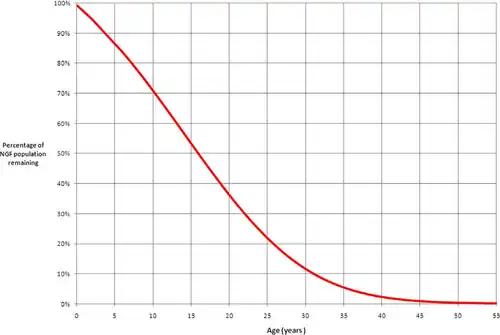

In 2010, researchers at the University of Edinburgh determined that by the time women are 30 years old, only 10% of their non-growing follicles (NGFs) remain.[4] At birth, women have all their follicles for folliculogenesis, and they steadily decline until menopause.